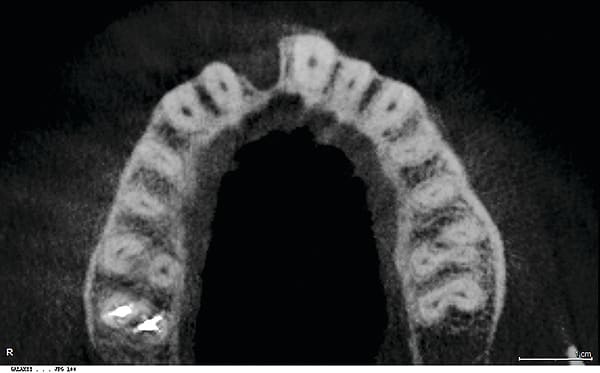

Figure 16

Figure 16 CBCT revealed 3-dimensionally sound implant placement No. 8; for optimum esthetic outcome, only a single implant for No. 8 was placed cantilevering pontic No. 7, avoiding central-lateral esthetic dilemma.